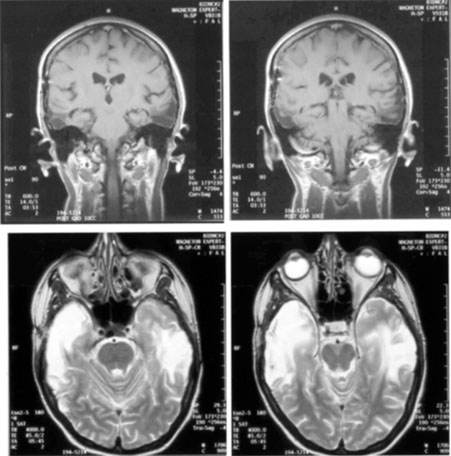

Most striate lesions are infarction, mainly from posterior cerebral artery occlusion (Fig. 14), with sudden onset visual loss and sometimes headache.53 In about half, the visual field defect is the only deficit,53 but in others damage to medial occipito-temporal regions causes amnesia, prosopagnosia, and color perception defects. A syndrome of agitated delirium and hemianopia occurs with lesions of the medial occipital lobe, parahippocampus, and hippocampus.54–56 Brainstem signs include impaired level of consciousness, III nerve palsy, dysarthria and hemiplegia.53 Causes of ischemia are most frequently cardiac emboli and vertebrobasilar occlusive disease; migraine is a rare cause of permanent defects.53 Hemorrhage, vascular malformations, primary and secondary malignancies are much less common.33

Fig. 14. Location and etiology of homonymous hemianopia in 140 patients. (From Fujino T, Kigazawa K, Yamada R: Homonymous hemianopia. A retrospective study of 140 cases. J Neuroophthalmol 6:17, 1986, Aeolus Press, with permission.)